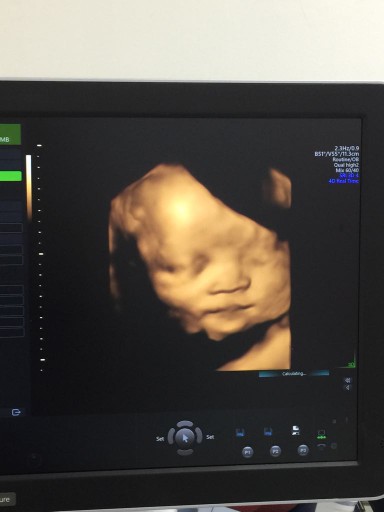

28w4d ค่ะ